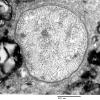

PERIPHERAL NEUROPATHY

18 HEREDITARY DISORDERS

Charcot-Marie-Tooth 1 (CMT-1) (6)